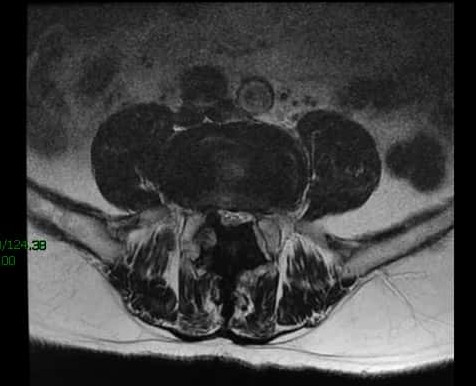

核磁上可见椎4/5间孔狭窄,神经根受压变形。

核磁上可见椎间孔狭窄,神经根受压变细。